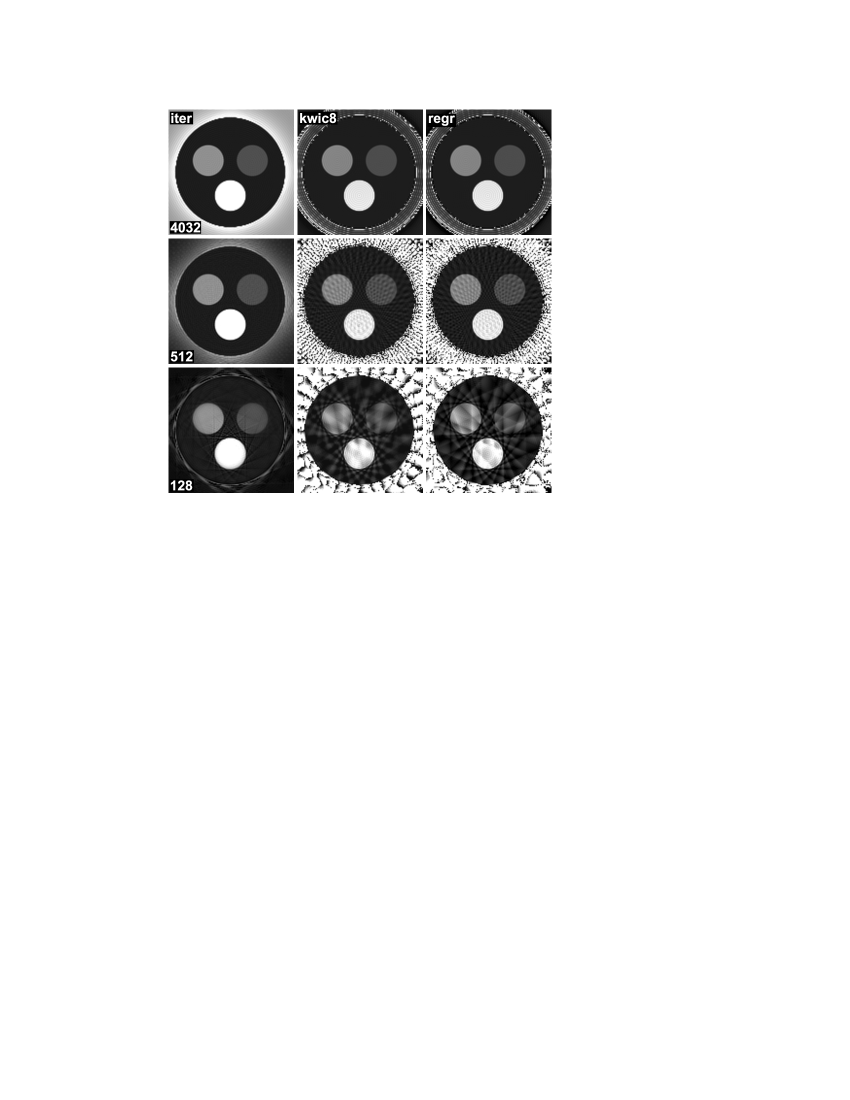

Finally, Fig. 4 shows iterative reconstructions of the human brain from radial data with different degrees of undersampling, ranging from a total of 512 spokes (32 repetitions) to only 128 spokes (8 repetitions). As expected, the data reduction is accompanied by some loss of image quality, but even for 128 spokes the iterative approach still offers a relatively good separation of proton density and relaxivity. For comparison, relaxivity maps obtained by the KWIC approach are shown in the bottom row, and it can be seen that the image quality breaks down for higher degrees of undersampling.

5.2 Accuracy

Data set True T2 Iterative KWIC8 Gridding 4032 spokes Compartment 1 50 ms ms ms ms Compartment 2 100 ms ms ms ms Compartment 3 200 ms ms ms ms Surrounding 1000 ms ms ms ms 512 spokes Compartment 1 50 ms ms ms ms Compartment 2 100 ms ms ms ms Compartment 3 200 ms ms ms ms Surrounding 1000 ms ms ms ms 128 spokes Compartment 1 50 ms ms ms ms Compartment 2 100 ms ms ms ms Compartment 3 200 ms ms ms ms Surrounding 1000 ms ms ms ms